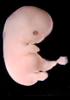

Carnegie Stage 20 (50 post-ovulatory days)

Most embryos at stage 20 are approximately 50-51 postovulatory days old and measure 21-23 mm in length. Distinguishing criteria for this stage include upper limbs slightly bent at the elbows, short stubby fingers, hands curving over the cardiac region but still far apart from each other, and a fringe-like vascular plexus that marks growth centers laterally in the superficial tissues of the head.

Although some of the photographs below show abnormal embryos, the animations and MRI slice images all depict normal embryos. Abnormal embryos are noted in the titles of the large photos when they are opened.